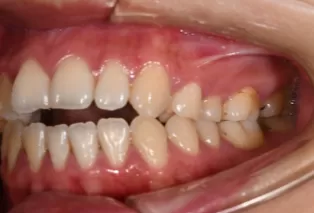

Intraoral photos